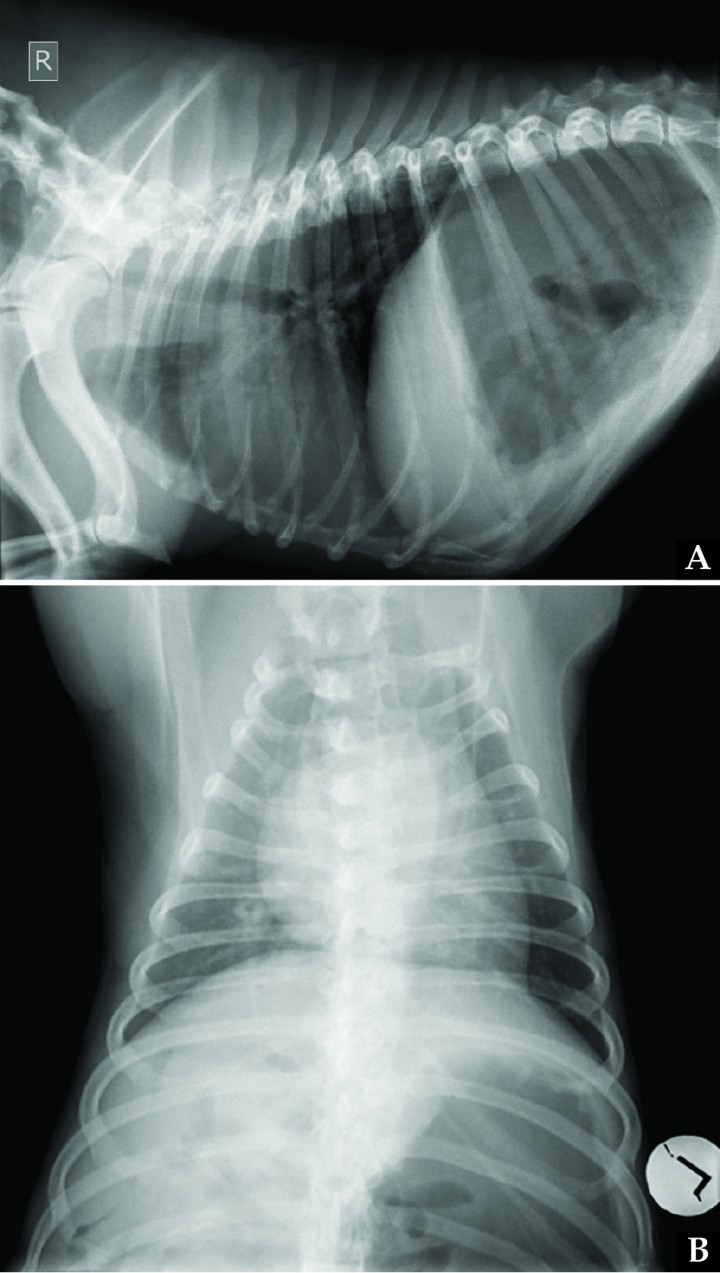

Pleural space diseases, diaphragmatic disorders, and pulmonary parenchymal diseases were assessed most likely based on the paradoxical abdominal respiratory pattern and the absence of noisy breathing. Thoracic radiographs (Fig. 2) showed bilateral cranial displacement of the diaphragm and small lung field. On the left lateral view, the left crus intersected the spine at the cranial border of T9, while on the right lateral view, the right crus intersected the spine at the cranial border of T10; on the dorsoventral view, the most cranial edge of the diaphragm was visible at the level of the cranial border of T8. Diffuse increased opacity of the entire lung field was observed, consistent with poor lung inflation. Cardiovascular structures appeared normal. According to the vertebral heart score system, cardiac silhouette measured 11.6 vertebral units including thoracic hemivertebrae (reference interval in Bulldogs with abnormal vertebrae, 11.8 to 15 vertebral units).[ Jepsen-Grant K, Pollard RE, Johnson LR. Vertebral heart scores in eight dog breeds. Vet Radiol & Ultrasound 2013; 54:3-8. [PubMed] ] Severe gastric distension with gas was also observed in the cranial abdomen.

<p>(A) Right lateral and (B) dorsoventral thoracic radiographs of the same dog in Figure 1 on admission. Due to bilateral diaphragmatic paralysis, cranial diaphragmatic displacement is present, with subsequent poor lung inflation and increased opacity of the lung field. Gastric dilation is also visualized.</p>

(A) Right lateral and (B) dorsoventral thoracic radiographs of the same dog in Figure 1 on admission. Due to bilateral diaphragmatic paralysis, cranial diaphragmatic displacement is present, with subsequent poor lung inflation and increased opacity of the lung field. Gastric dilation is also visualized.